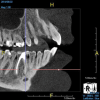

(4.) In a CBCT image axial view, the MB1 and MB2 canals are readily visible in tooth No. 14, and in the coronal view, these two separate canals can be seen to merge into a single apical opening.

Figure 4

(5.) In a CBCT image axial view, the MB1 and MB2 canals are readily visible in tooth No. 14, and in the coronal view, these two separate canals can be seen to merge into a single apical opening.

Figure 5